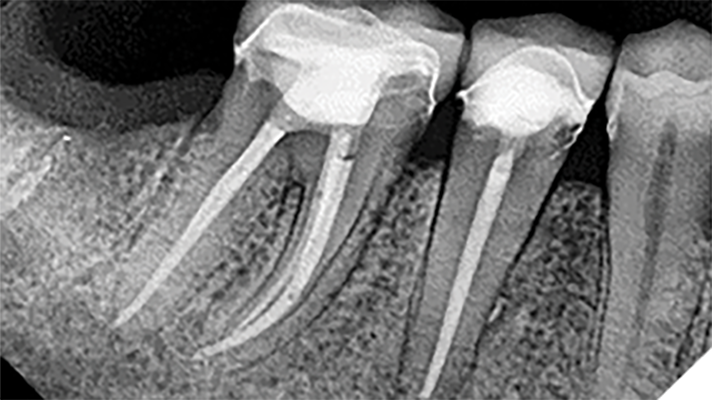

Why Endodontic Therapy is the Treatment of Choice in Patients on Anti-Resorptive Drug Therapy

The most common odontogenic infection is that of the periapical tissues most frequently caused by dental caries, a deep restoration, or failed root canal treatment.1 Apical periodontitis (AP) has been found to have a prevalence of 50% in patients under the age of 50, and the prevalence and risk of AP has been found to be … Read more